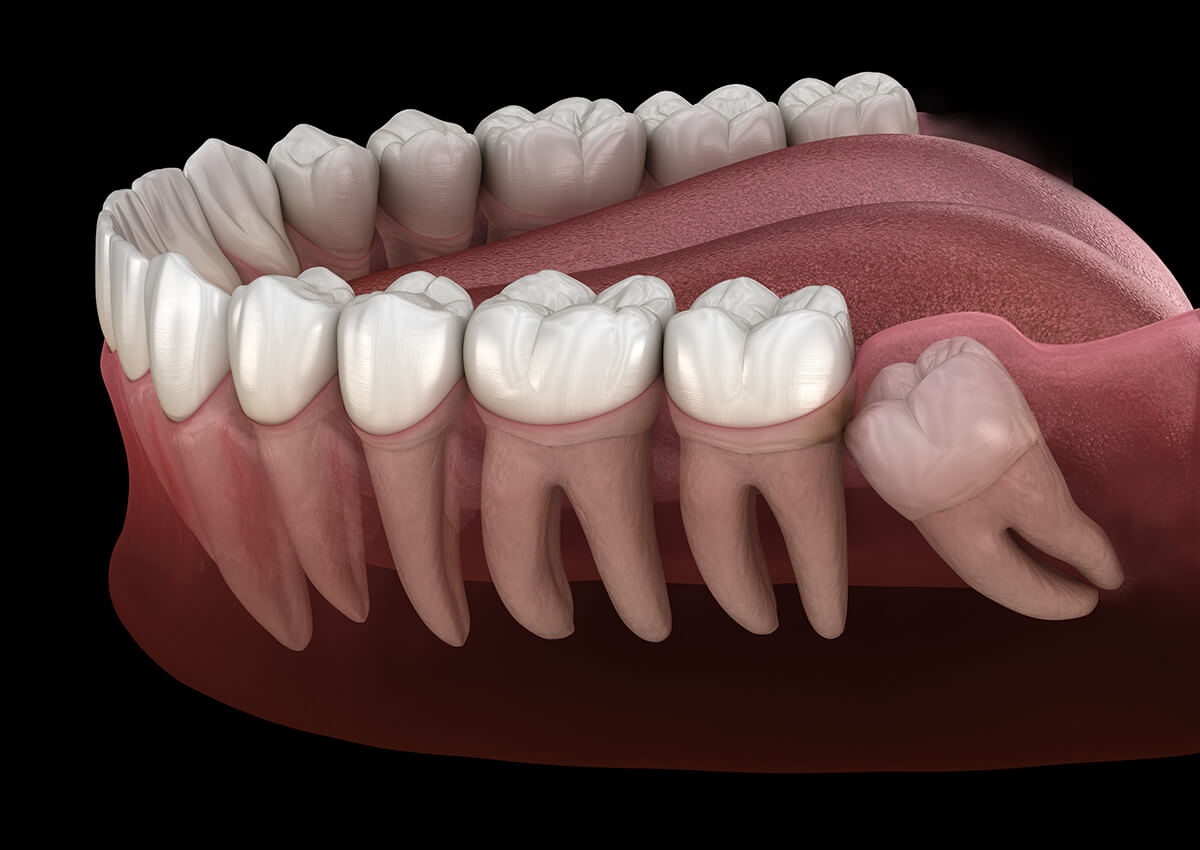

Wisdom tooth surgery is a surgical procedure to remove one or more wisdom teeth — the four permanent adult teeth located at the back corners of your mouth on the top and bottom.

If a wisdom tooth doesn't have room to grow (impacted wisdom tooth), resulting in pain, infection or other dental problems, you'll likely need to have it pulled out.

They’re impacted.

Because they're so far back in your mouth, wisdom teeth may not come in normally. They can be trapped in your jawbone or gums, which can be painful.

They come in at the wrong angle.

They may press against your other teeth.